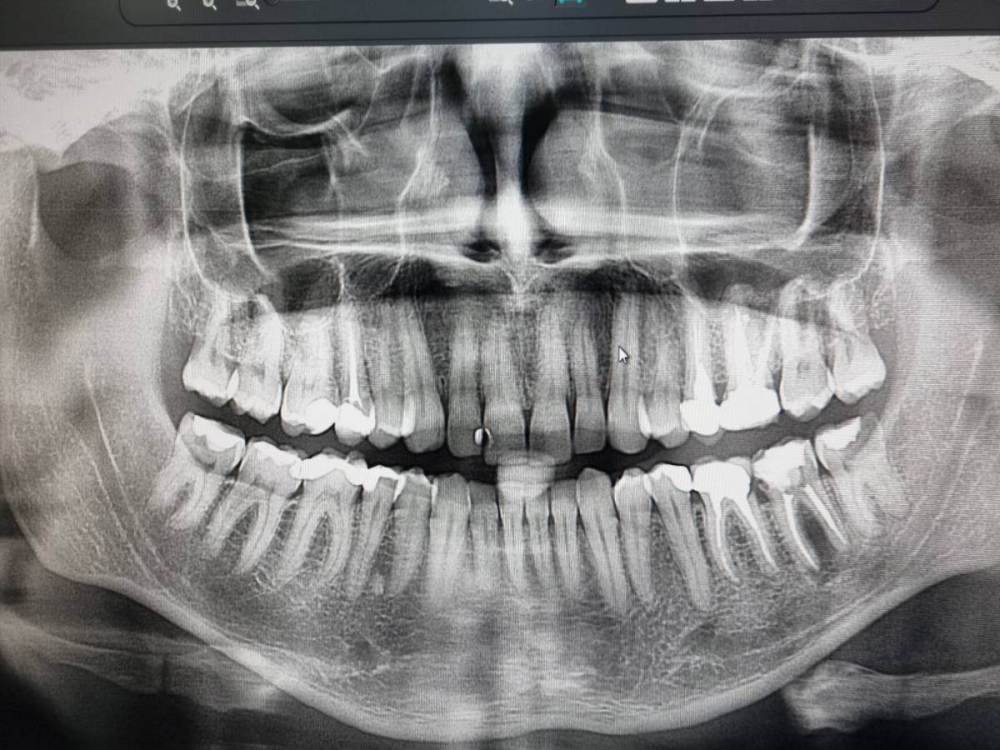

Chelovek2012 Опубликовано 20 апреля, 2023 Автор Поделиться Опубликовано 20 апреля, 2023 Вот рентген, год назад Мне 38 лет Ссылка на комментарий

IvanK Опубликовано 21 апреля, 2023 Поделиться Опубликовано 21 апреля, 2023 Здравствуйте, год - это уже срок, не очень актуально, но, исходя из этого снимка, я бы рекомендовал: проверить контактный пункт 15-16, состояние пломб 11,12, на 25 возможно кариес под коронкой 15, 26, 37 оценить по дкт корни, далее протезирование 36 кариес под коронкой оценка контактных пунктов 45-46-47 1 Ссылка на комментарий

Chelovek2012 Опубликовано 21 апреля, 2023 Автор Поделиться Опубликовано 21 апреля, 2023 Спасибо за детальный анализ. А что вы рекомендуете сделать с моими зубами мудрости? У меня они есть, но состояние их - дальняя стенка повреждена. Как вы считаете, с дальней стороны реально стоматологу подлезть и запломбировать зуб? Или пока не болят, оставить, пускай будут? Я слышал что в США рекомендуют сохранять максимум зубов, которые возможно сохранить. Что-то в 38 лет зубы у меня не очень, уже есть 3 коронки и судя по вашему анализу, еще намечаются + замена существующих. Ссылка на комментарий

IvanK Опубликовано 22 апреля, 2023 Поделиться Опубликовано 22 апреля, 2023 23 часа назад, Chelovek2012 сказал: Спасибо за детальный анализ. на здоровье 23 часа назад, Chelovek2012 сказал: А что вы рекомендуете сделать с моими зубами мудрости? я бы рекомендовал их удалить, но не стал об этом писать, так как Вы пока к этому не готовы и есть другие проблемы, к 8кам можно подойти после основного лечения или в процессе 1 Ссылка на комментарий